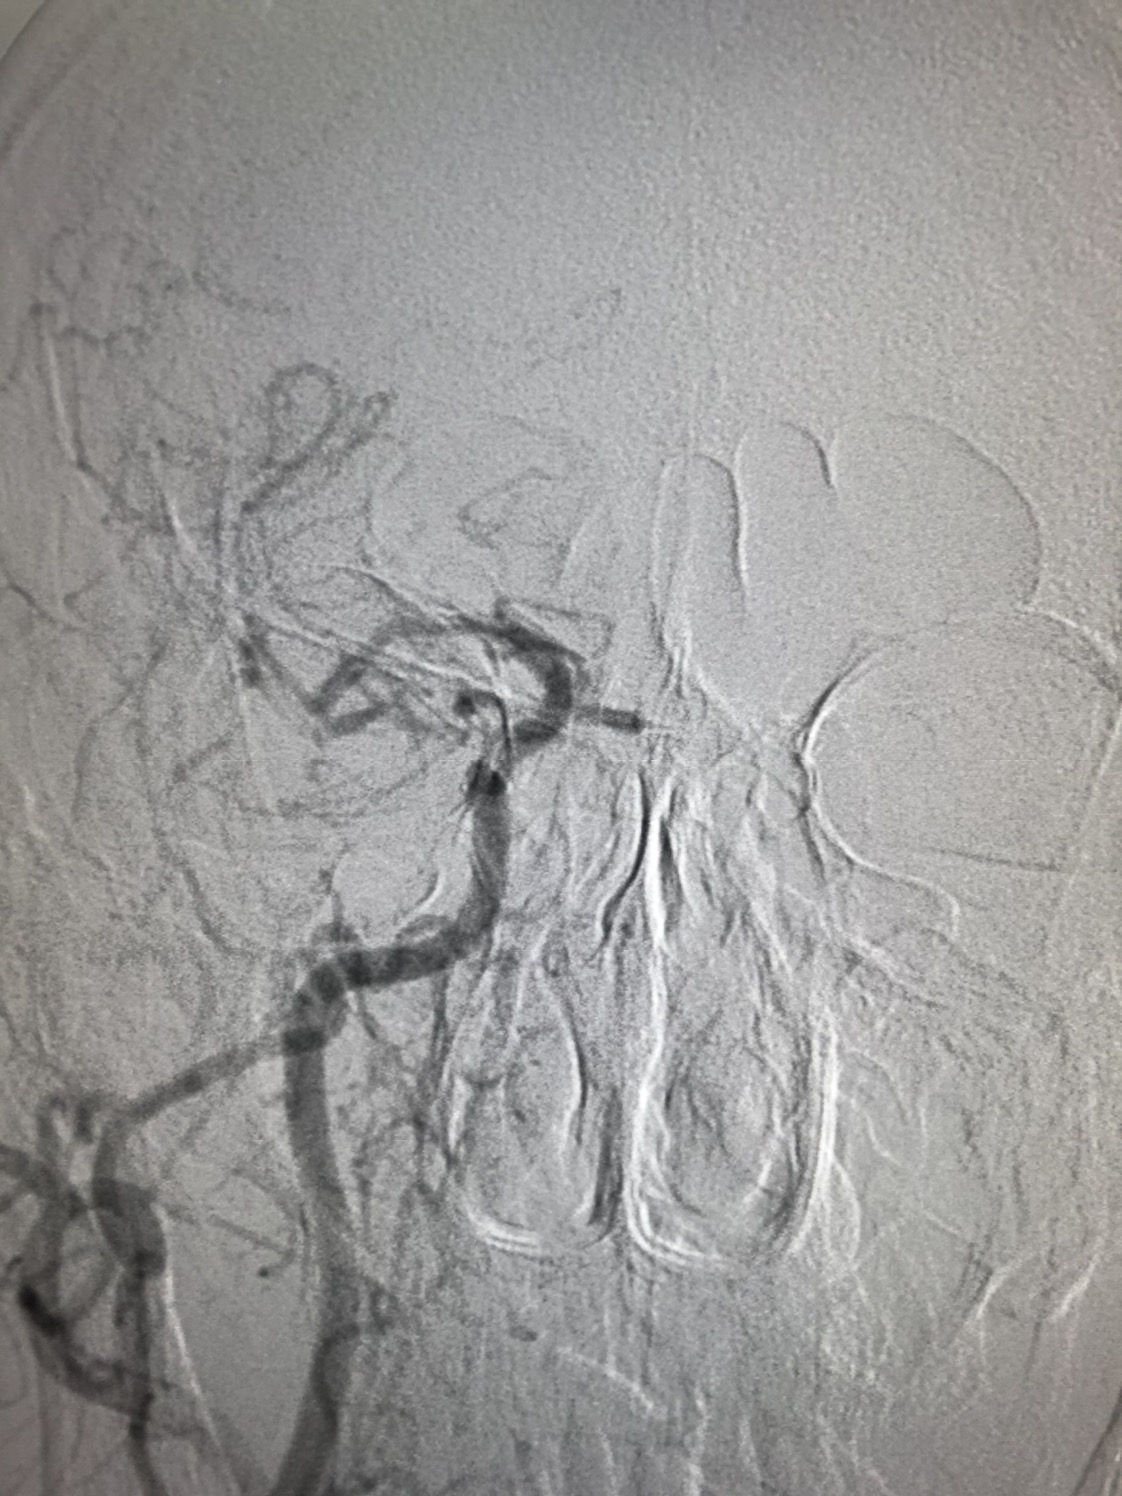

术后颅内血供明显改善,胚胎型大脑后动脉显影良好。